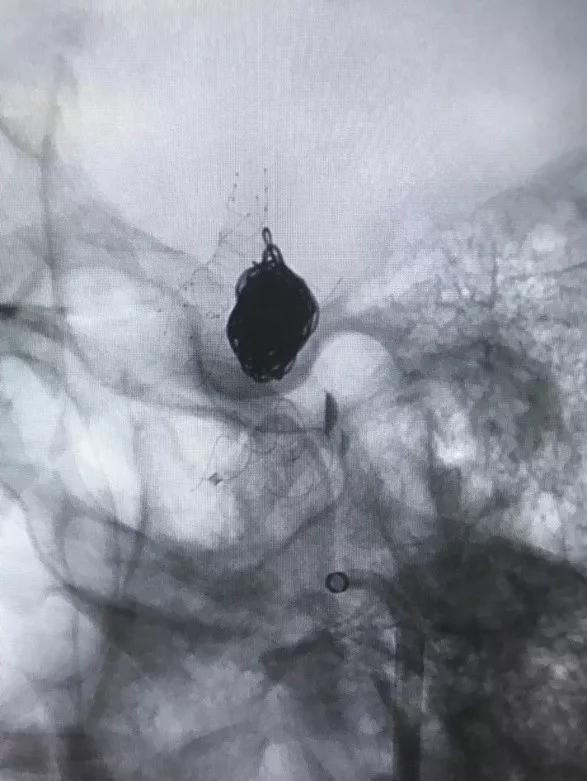

▲各角度观察显示Tubridge®贴壁良好

▲造影见造影剂滞留,载瘤动脉通畅。